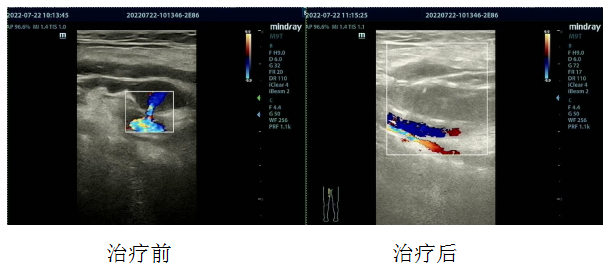

近日,超声科成功为一患者完成超声引导下假性动脉瘤封堵术。患者曹某,78岁女性,因“冠心病、心绞痛、高血压病3级(极高危)”于我院心内科住院治疗,期间,行彩超检查发现右侧股浅动脉假性动脉瘤;由于假性动脉瘤有破裂的危险性,因此积极的治疗是必须的。

研究表明:超声引导下注射凝血酶栓塞治疗假性动脉瘤,栓塞成功率高达94%-100%,而且并发症发生率极低。穿刺前认真仔细交代相关情况及穿刺后注意事项,彩色多普勒超声确定假性动脉瘤的部位、大小、瘤颈宽度、瘤颈与动脉关系。超声引导下将穿刺针经皮准确穿刺入假性动脉瘤瘤腔内,针尖避开瘤颈部,超声监测下缓慢注射稀释的凝血酶,实时观察瘤腔内血凝块形成情况;穿刺中及穿刺后无不良反应。术后超声监测未见明显活动性血流存在,局部加压包扎,安全返回病房。